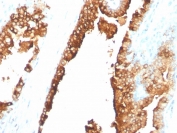

IHC analysis of formalin-fixed, paraffin-embedded normal human spleen stained with CDw75 antibody (clone LN1).

Recognizes a neuraminidase-sensitive sialoprotein (CDw75), present on cell membrane and cytoplasm of germinal center B-cells and derived lymphomas. This mAb reacts with RBC precursors of bone marrow, ductal and ciliated epithelial cells of kidney, breast, prostate, pancreas, lung, and with glioblastomas, astrocytomas, and Reed Sternberg cells in lymphocyte predominant Hodgkin s disease. It is shown to be a helpful antibody for ascribing a B-cell phenotype in known lymphoid tissues.